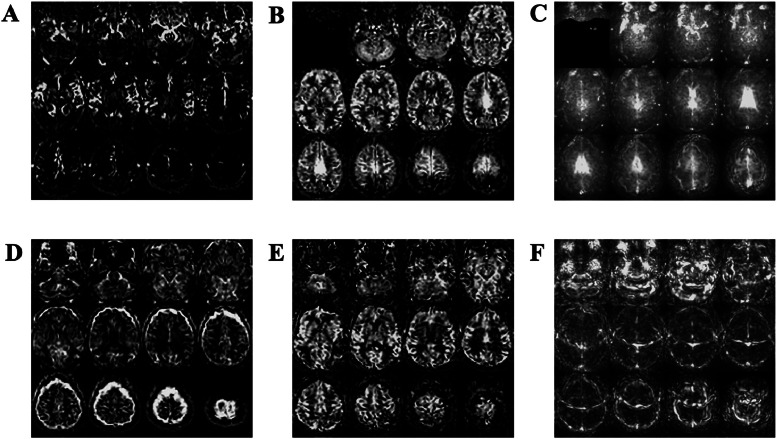

Arterial spin labelling (ASL) enables non-invasive quantification of regional brain perfusion using MRI. ASL was used in the Reducing Pathology in Alzheimer's Disease through Angiotensin TaRgeting (RADAR) multi-centre trial to pilot the assessment of the effects of the anti-hypertension drug losartan on cerebral blood flow (CBF). In the multi-centre setting, disparities in ASL implementation on scanners from different manufacturers lead to inherent differences in measured CBF and its associated parameters (e.g. spatial coefficient of variation (sCoV) of CBF, a proxy of arterial arrival times). In addition, differences in ASL acquisition parameter settings can also affect the measured quantitative perfusion values. In this study, we used data from the RADAR cohort as a case study to evaluate the site-dependent systematic differences of CBF and sCoV, and show that variations in the readout module (2D or 3D) and the post-labelling delay acquisition parameter introduced artifactual group differences. When accounting for this effect in data analysis, we show that it is still possible to combine ASL data across sites to observe the expected relationships between grey matter CBF and cognitive scores. In summary, ASL can provide useful information relating to CBF difference in multi-centre therapeutic trials, but care must be taken in data analysis to account for the inevitable inter-site differences in scanner type and acquisition protocol.